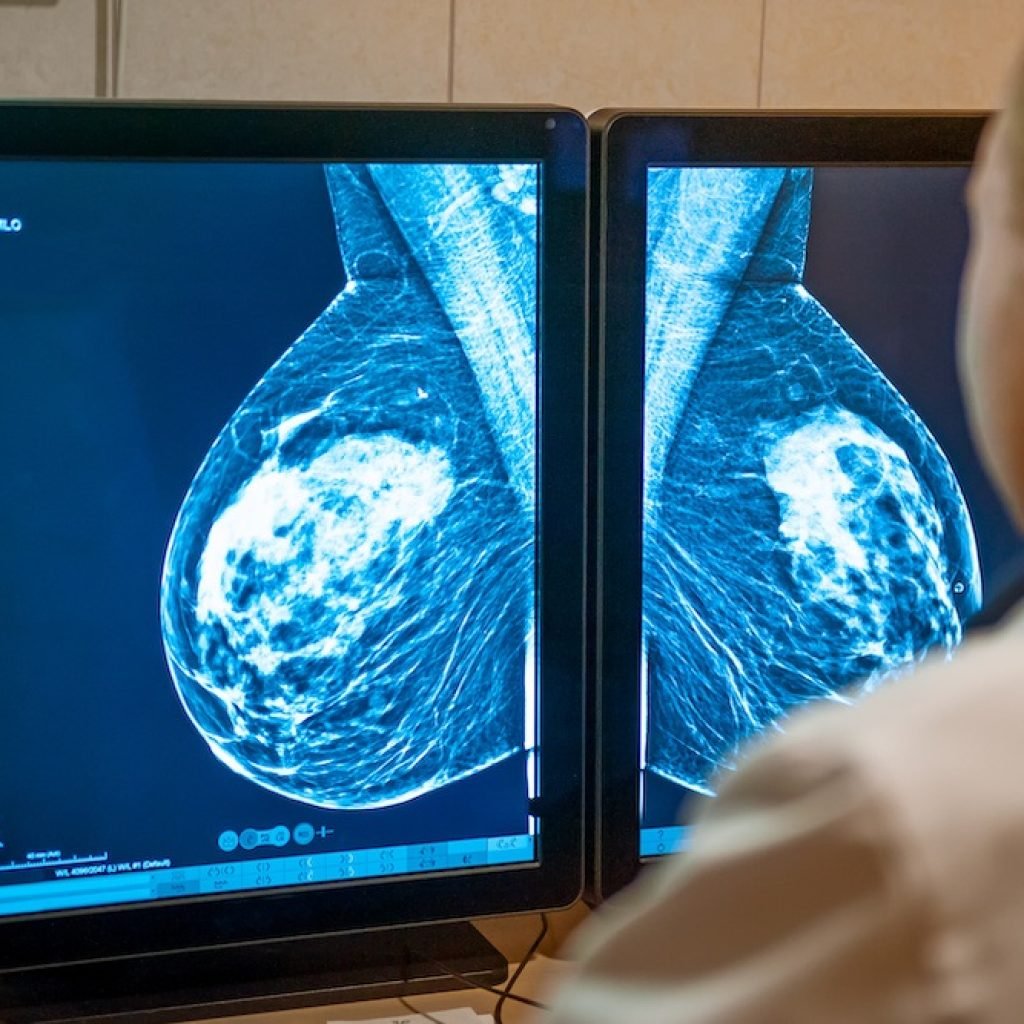

En un contexto donde la mortalidad por cáncer de mama en México alcanza 19.8 defunciones por cada 100 mil mujeres, ALIA Health y ÜMA Tech IA anunciaron el desarrollo conjunto de ALIA Health Risk Platform, una solución basada en inteligencia artificial que permite predecir la probabilidad futura de desarrollar cáncer de mama a cinco años, a partir de mamografías de rutina.

Actualmente, solo 27 por ciento de las mujeres en edad de riesgo accedió a una mastografía en el último año, mientras que cerca de 64 por ciento de los casos se detectan en etapas II o III, cuando los tratamientos son más complejos y costosos. Se estima que la atención de un caso avanzado puede superar los 300 mil pesos por paciente, generando un alto impacto financiero en el sistema de salud.

ALIA Health es una spin-off científico-tecnológica de TecSalud, el sistema de salud del Tecnológico de Monterrey. La plataforma integra Mammorisk+, un modelo predictivo entrenado con datos reales de práctica clínica, diseñado para estimar el riesgo de desarrollar cáncer de mama en un horizonte de cinco años, incluso cuando las mamografías no presentan hallazgos sospechosos.

El objetivo es intervenir antes del diagnóstico, en la etapa en la que se definen estrategias de prevención, seguimiento y personalización del tamizaje.

ALIA Health Risk Platform busca contribuir a una estratificación personalizada del riesgo, permitiendo priorizar recursos, reducir intervenciones innecesarias y apoyar decisiones clínicas más precisas tanto en instituciones públicas como privadas.

En un entorno donde el acceso al tamizaje mamográfico sigue siendo desigual en México y América Latina, la predicción individualizada representa una herramienta clave para mejorar la equidad en salud y fortalecer modelos de prevención basados en datos.